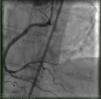

A previous nuclear stress test performed by the primary care provider before the diagnosis of aortic stenosis revealed a large area of inferior wall ischemia. Consequently, we scheduled an invasive coronary angiogram with left and right heart catheterization, which showed a heavily calcified ostial right coronary artery obstructive lesion of 99% (Figure 1) combined with critical aortic stenosis (mean transaortic PG of 44 mmHg and an AVA of 0.3 cm2).